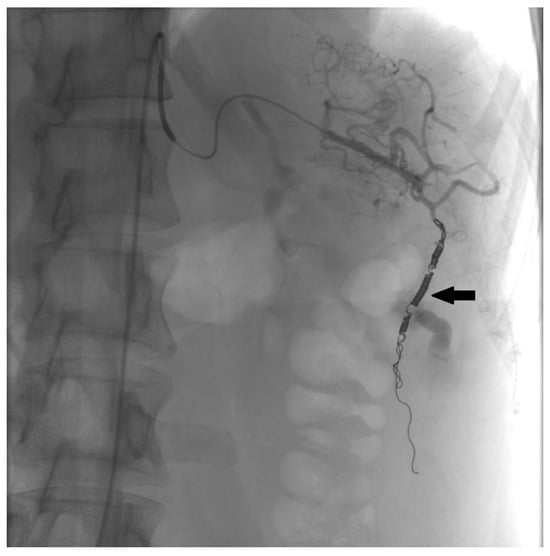

- Shah, M.; Patel, P.; Redstone, E.; Li, Z. Preoperative splenic artery embolization for splenic ectopic pregnancy. Radiol. Case Rep. 2022, 18, 285–288. [Google Scholar] [CrossRef]

- Klang, E.; Keddel, N.; Inbar, Y.; Rimon, U.; Amitai, M. Splenic Pregnancy: A New Minimally Invasive Approach to Treatment. Cardiovasc. Intervent. Radiol. 2016, 39, 1339–1342. [Google Scholar] [CrossRef]

- Makrigiannakis, A.; Raissaki, M.; Vrekoussis, T.; Patramani, S.; Makrygiannakis, F.; Kholcheva, N.; Tsetis, D. Splenic pregnancy treated with transcatheter embolization and methotrexate. Arch. Gynecol. Obstet. 2021, 303, 55–59. [Google Scholar] [CrossRef] [PubMed]